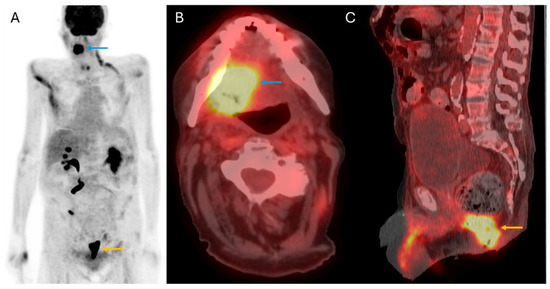

5. Distant Disease Detection